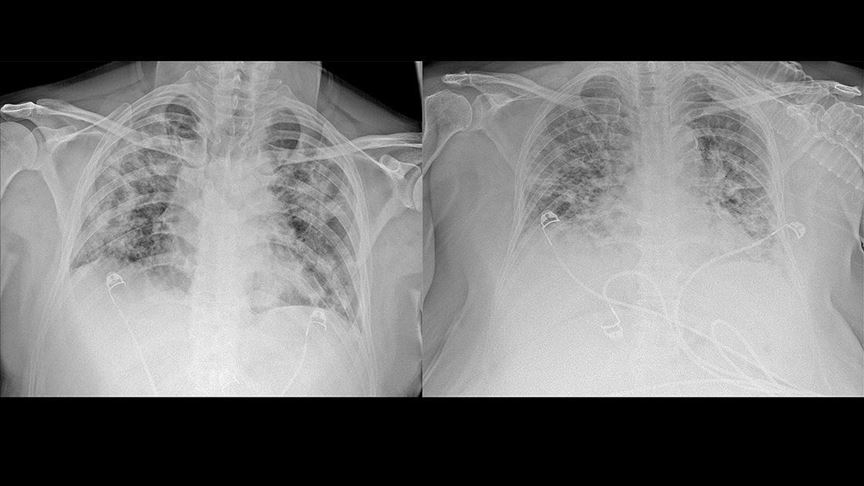

Covid-19 pnömonisinde akciğer tutulumunun genellikle iki taraflı ve çok sayıda odak halinde görüldüğünü aktaran Yavuz, şunları kaydetti:

"Belirtilerin başladığı ilk 4-5 günde akciğerde tek odak olarak başlayan lezyonların sayı ve büyüklüğü tedaviye geç başlanması durumunda 7-10 gün içinde artmaktadır. Bazen tedaviye zamanında başlansa bile yayılım görülmekte ancak iyileşme süreci daha hızlı ve çoğunlukla sekelsiz olmaktadır. Tedavide amaç hastanın solunum sıkıntısının giderilmesi, hastalığın yayılmasının yavaşlatılması/durdurulması veya en az hasarla iyileşmenin tamamlanmasıdır. Elimizde henüz uzun dönem verileri olmamakla beraber vakaların bir bölümünde, tedavinin 2. haftasında lezyonların gerilediği ve 6. hafta sonunda tamamen kaybolduğu izlenirken, bir bölümünde tamamen iyileşme sağlanamayıp akciğerde bant şeklinde 'atelektazi' dediğimiz büzüşmeler, alveol hasarları ve doku kayıpları görülmektedir."